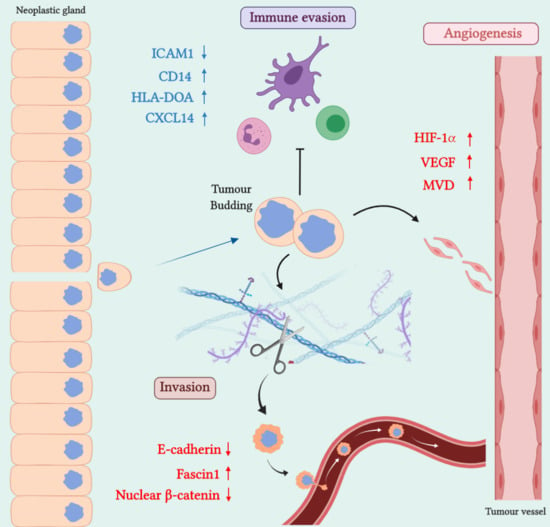

2. SAC Shows an Upregulation of Angiogenesis Markers

3. SAC is Especially Capable of Avoiding the Immune Response

4. SAC Displays an Active Invasive Front